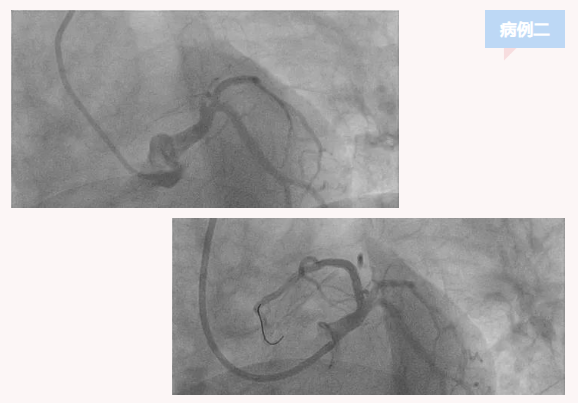

患者二,男,53岁,主因胸痛1小时来诊,急诊查心电图提示急性广泛前壁心肌梗死,急诊行介入治疗。造影提示前降支近段完全闭塞,其余冠脉基本正常,放置支架一枚,血流开通胸痛症状即刻缓解,住普通病房治疗一周后,康复出院。